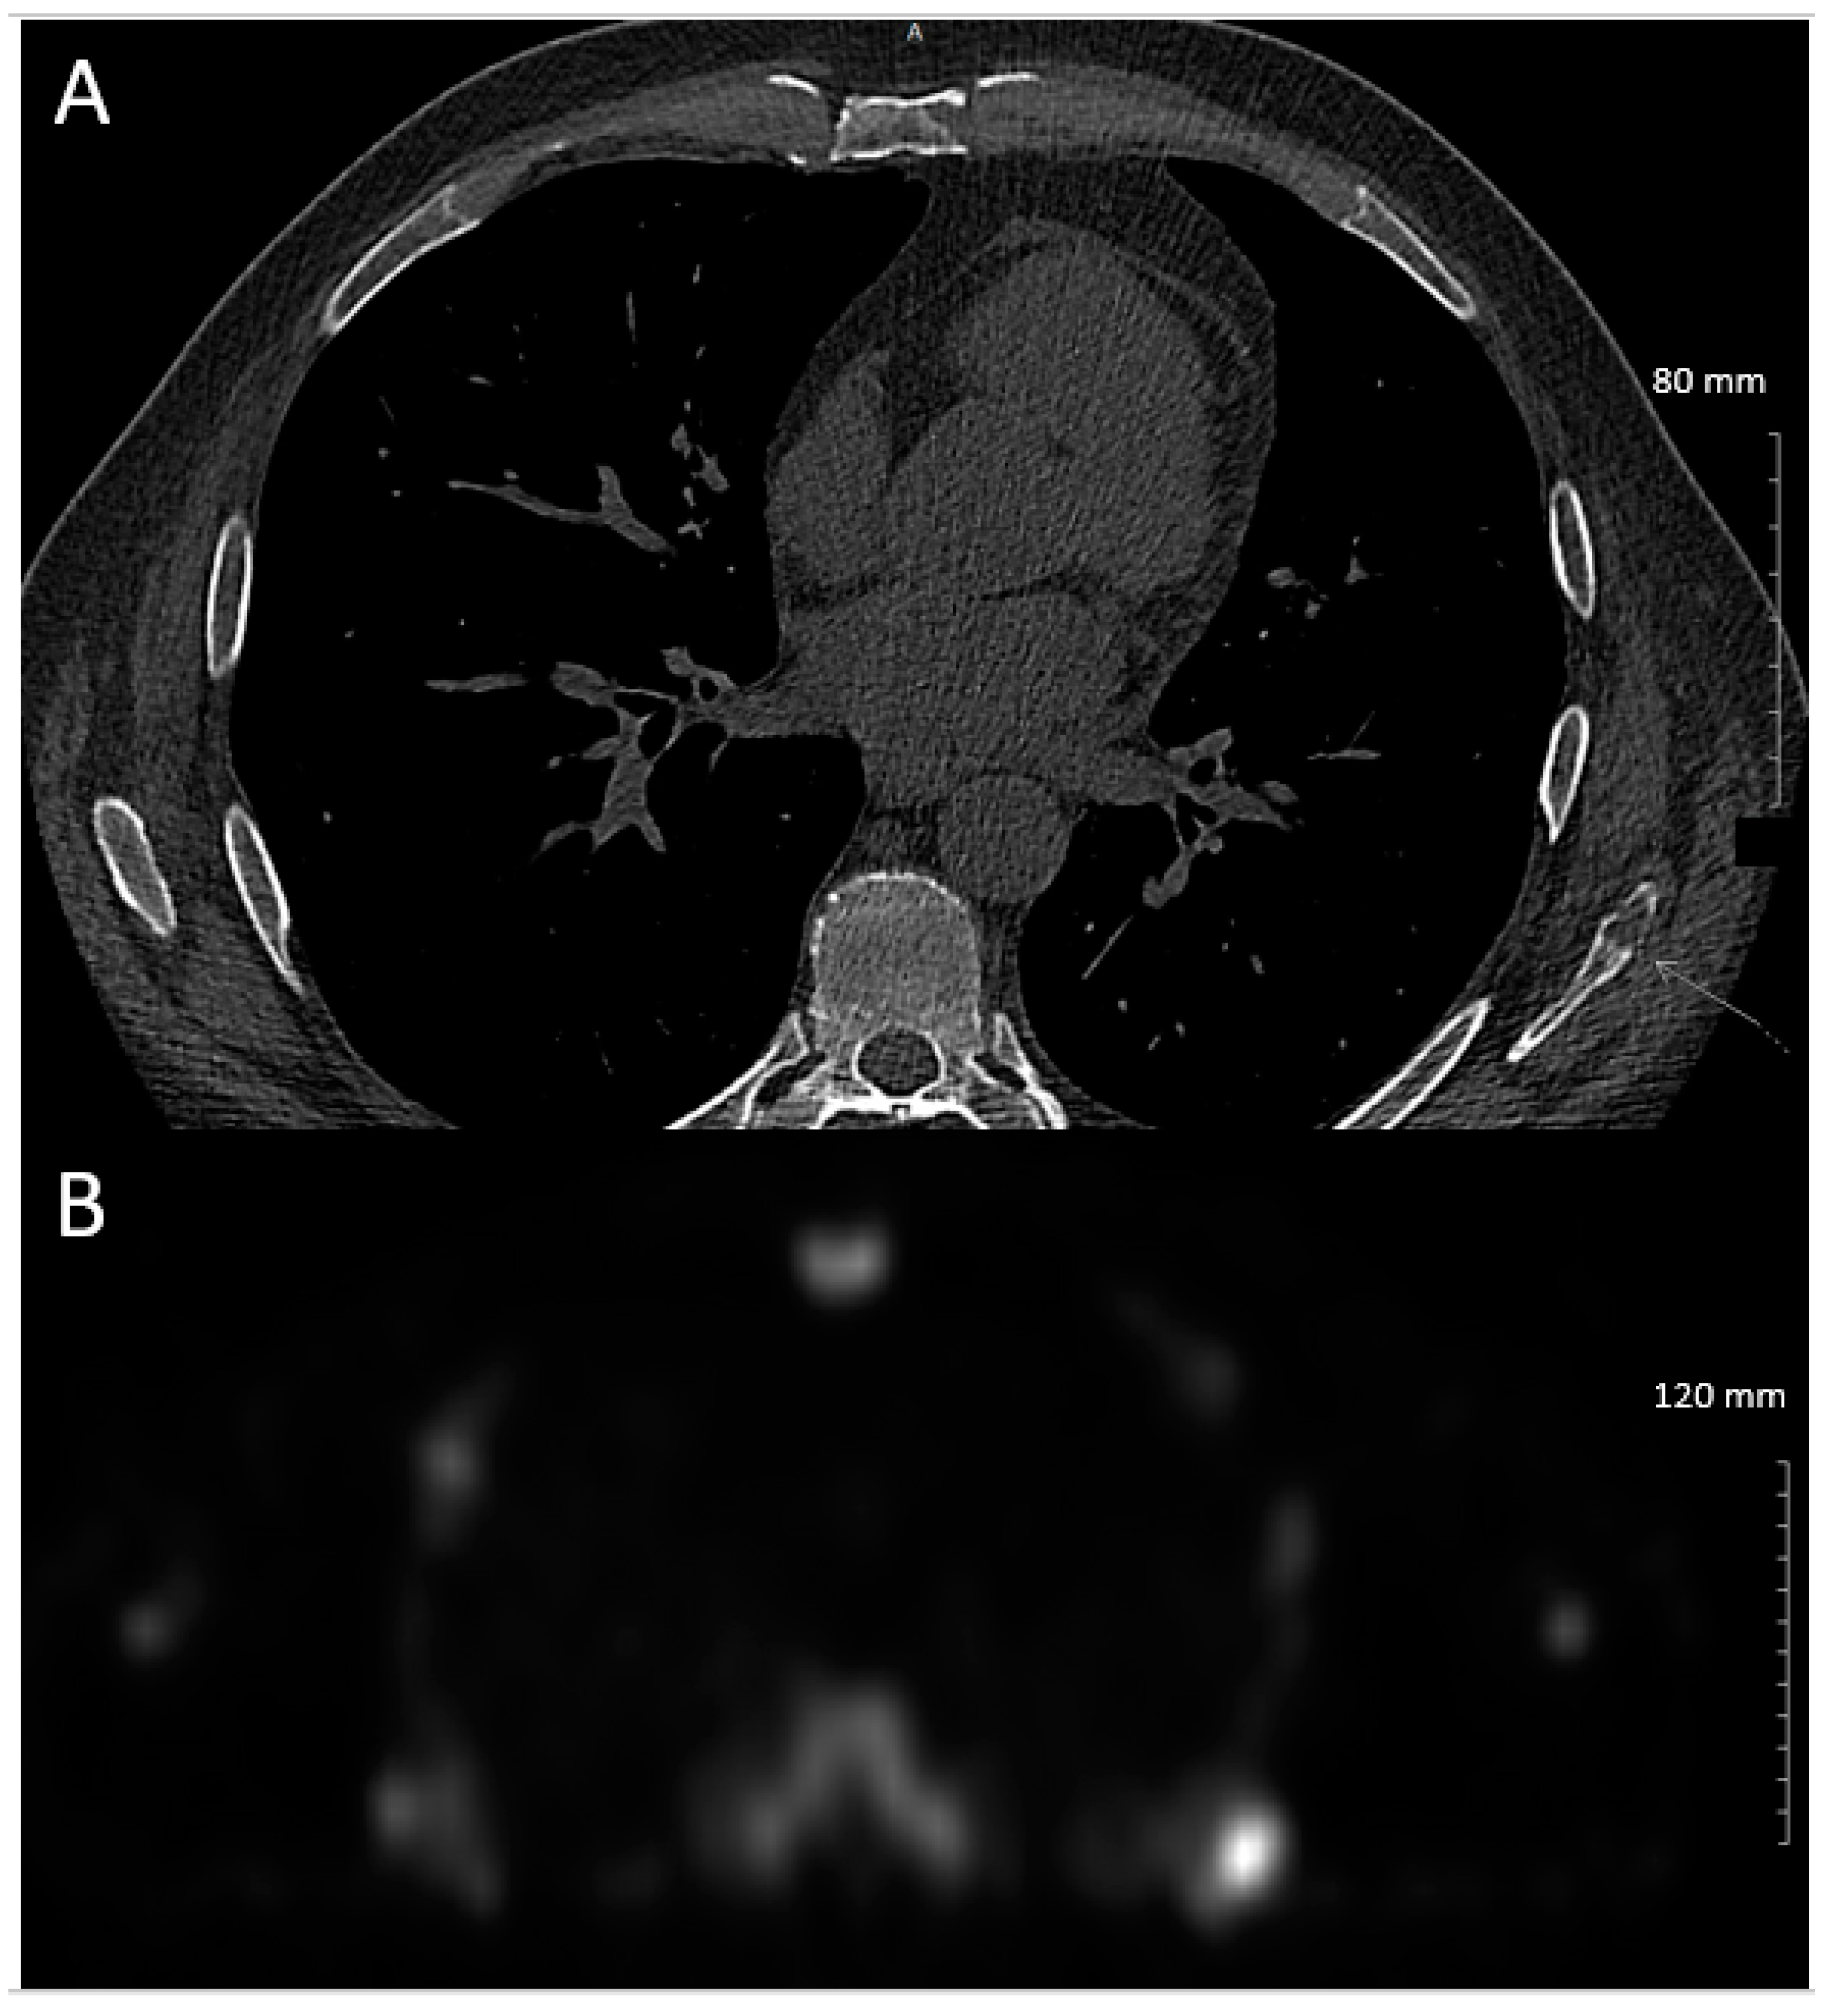

2. Case